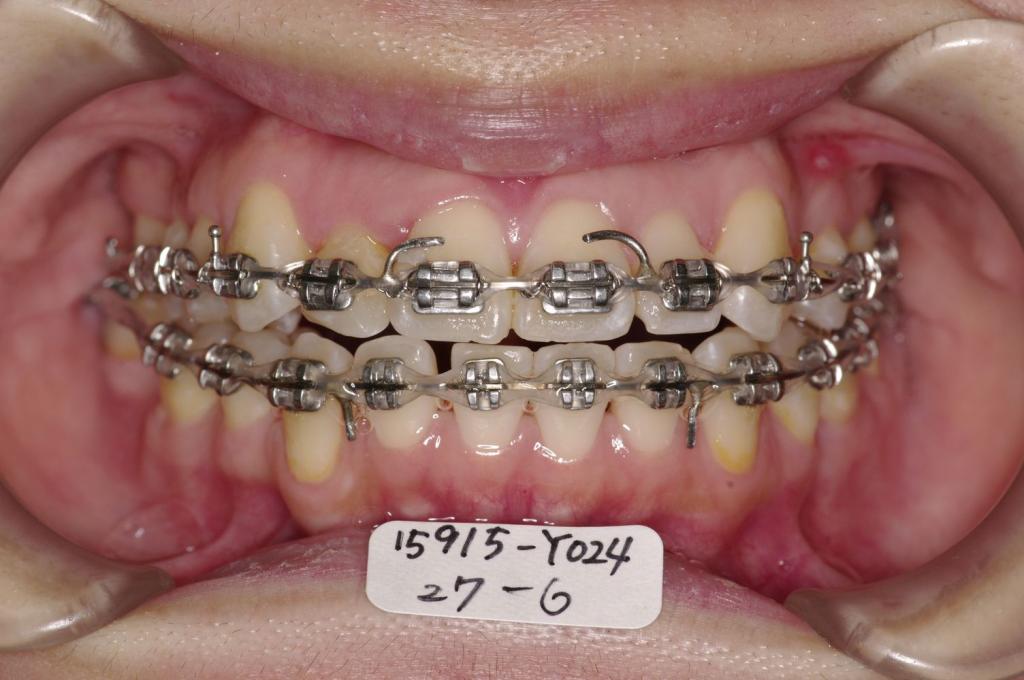

- 八重歯、咬み合わせ

- 上下の前歯の間に舌を入れる癖がある場合には、歯の裏側にフックを付ける場合があります。その場合発音がしにくくなったり、食事の時に舌が痛かったりすることがあります。